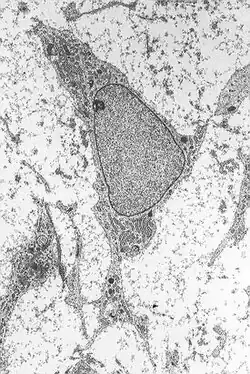

Mesenchymale Stammzellen (Mesenchymal stem cells, MSC) sind multipotente Vorläuferzellen verschiedener Zelltypen, die sich vom Mesenchym ableiten. Sie können sich unter anderem in Osteoblasten (Knochenzellen), Chondrozyten (Knorpelzellen), Myozyten (Muskelzellen) und Adipozyten (Fettzellen) differenzieren[1]. Außerdem konnte eine Differenzierung in Neurone, Astrozyten und Oligodendrozyten (Zellen des Nervensystems) beobachtet werden.[2]

Mesenchymale Stammzellen besitzen ein hohes Proliferations- und Differenzierungspotential. Adulte Mesenchymale Stammzellen tragen zur Aufrechterhaltung und Regeneration des Stütz- und Bindegewebes, wie Knochen, Knorpel, Muskel, Bändern, Sehnen und Fettgewebe bei. Darüber hinaus unterstützen sie Wachstum und Entwicklung der Vorläuferzellen des Blutes im Knochenmark (Hämatopoese).

MSC lassen sich aus fast allen Geweben (Knochenmark, Knorpel, Fettgewebe, Muskel, Lebergewebe, Blut, Amnionflüssigkeit) isolieren. Aufgrund des sehr hohen MSC-Anteils sowie der guten Zugänglichkeit werden MSC gerne aus dem Fettgewebe (z. B. aus Liposuktionsaspiraten) isoliert. Wegen der Heterogenität der Aufreinigungen wird heute der Begriff Mesenchymale Stamm/Stroma-Zellen (statt Mesenchyle Stammzellen) von der wissenschaftlichen Gemeinde bevorzugt. MSC lassen sich kultivieren und in vitro in unterschiedliche Zellen und Gewebe ausdifferenzieren. Die spezifische funktionale Differenzierung lässt sich durch Aktivierung bzw. Unterdrückung von Genen aktiv steuern; dabei kommt es zur die Hämatopoese unterstützenden Bildung von Knochenmarksstroma oder sie differenzieren in osteogene, chondrogene oder adipogene Zellen.